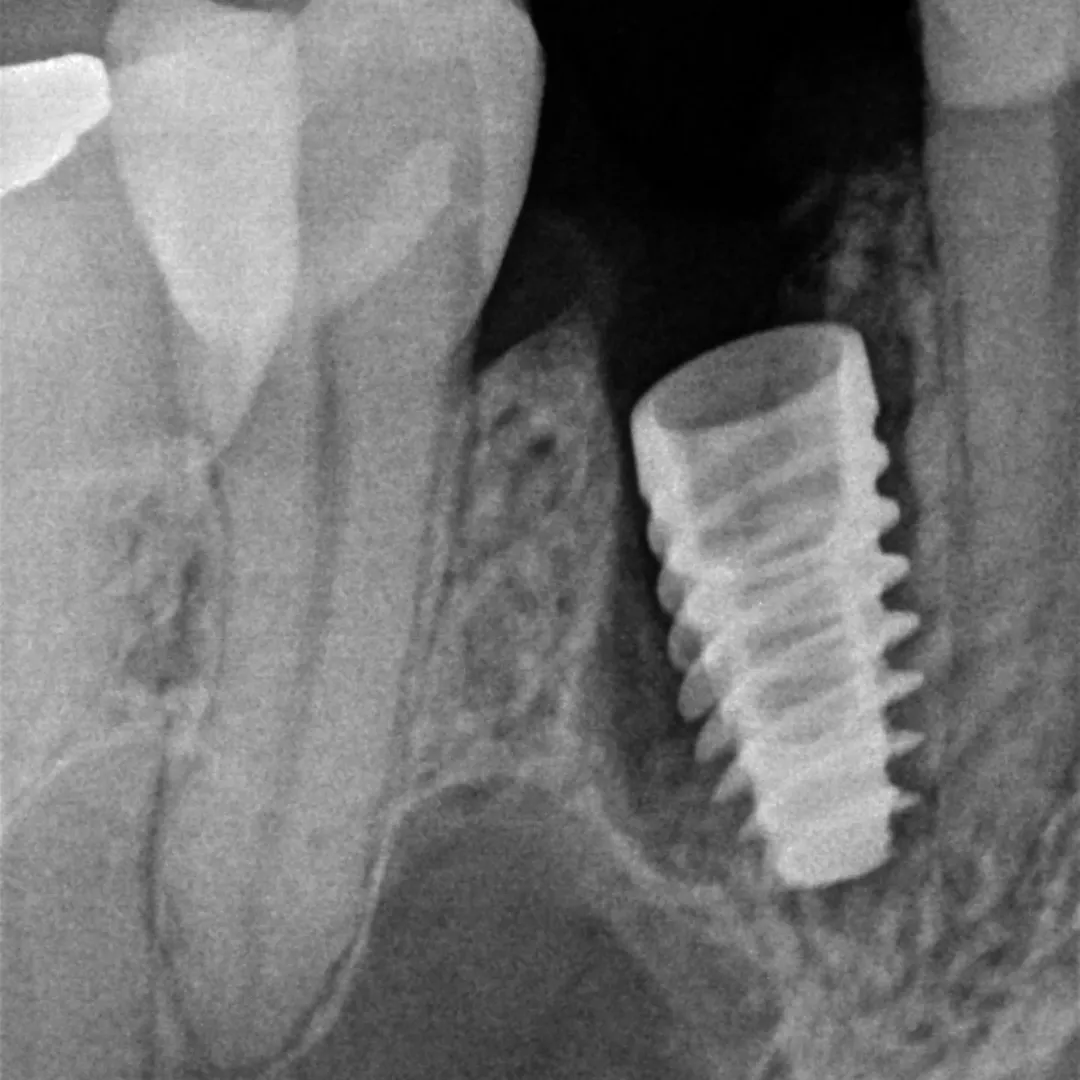

- Instalação do implante com posicionamento palatinizado: Coloquei o implante numa posição ligeiramente palatinizada, de forma a garantir o espaço ("gap") vestibular necessário entre o implante e a tábua óssea vestibular.

- Preenchimento do gap com biomaterial: Preenchi o espaço entre o implante e a tábua vestibular com osso (biomaterial), compensando a reabsorção fisiológica que ocorre naturalmente após a extração e mantendo o volume dos tecidos moles.

Nas imagens, é possível acompanhar a sequência completa: desde as radiografias iniciais com o dente comprometido, passando pela fase cirúrgica com a extração e colocação do implante, até ao provisório aparafusado em posição. A radiografia final confirma o bom posicionamento do implante e o preenchimento adequado do gap vestibular.